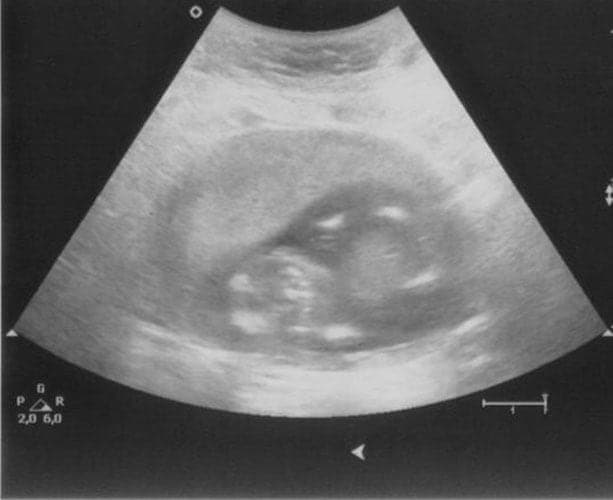

Ultraschallbilder aus dem 1. Trimester (1. SSW bis 12. SSW)

Im ersten Trimester sind die Ultraschallbilder meist noch schwer zu deuten. Oft erkennt man in den letzen Wochen des ersten Trimesters gut den Körper, den Kopf und die Gliedmaße. Das Geschlecht kann man in dieser Zeit meist noch nicht erkennen.